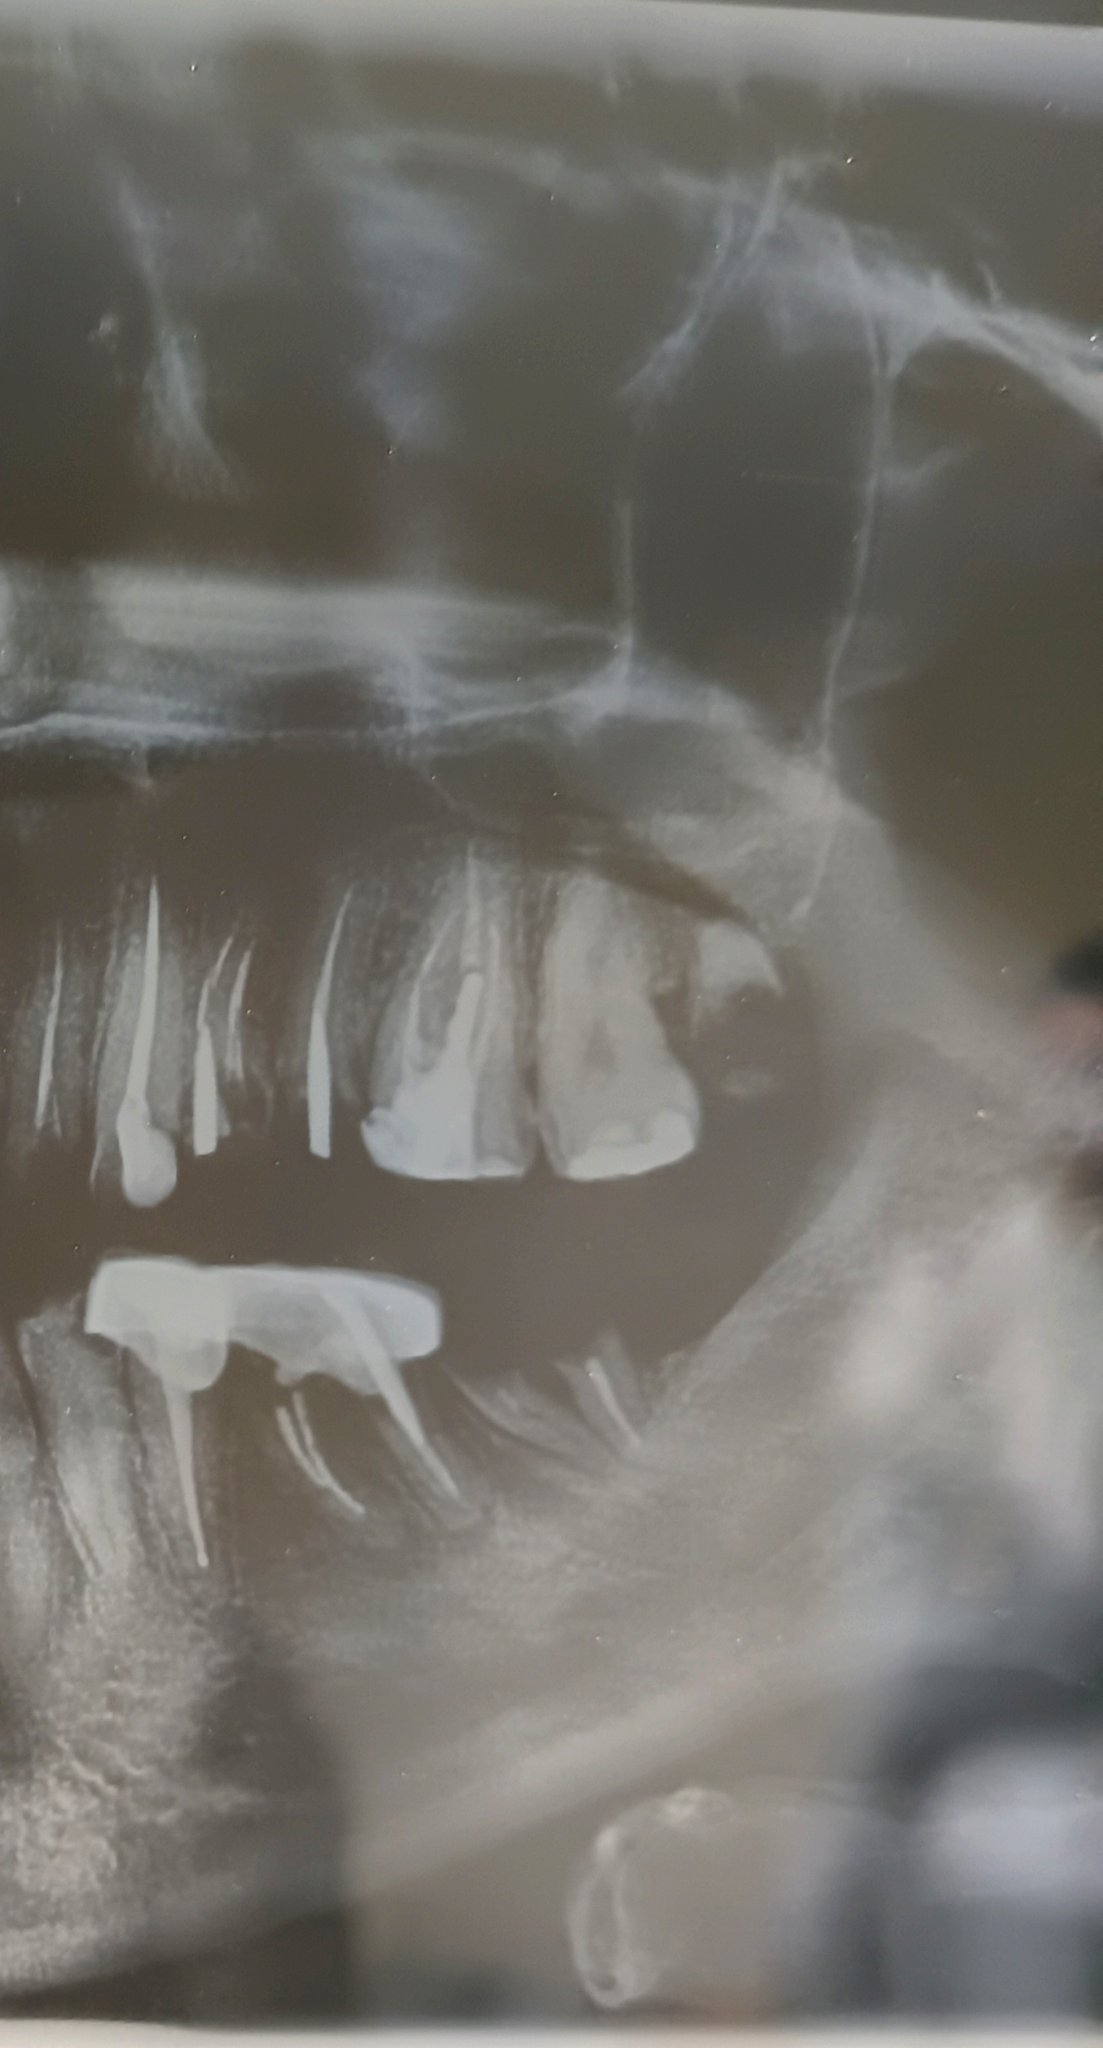

Какво може да причини постоянна болка след екстракция на нерв на зъб?

Постоянната болка след екстракция на нерв на зъб може да бъде причинена от неправилно лечение, неправилно кореново запълване или възпаление на кореновите канали. Обикновено болката трябва да намалее в рамките на 2-3 дни след процедурата. Ако болката продължава, препоръчително е да се консултирате със зъболекар.